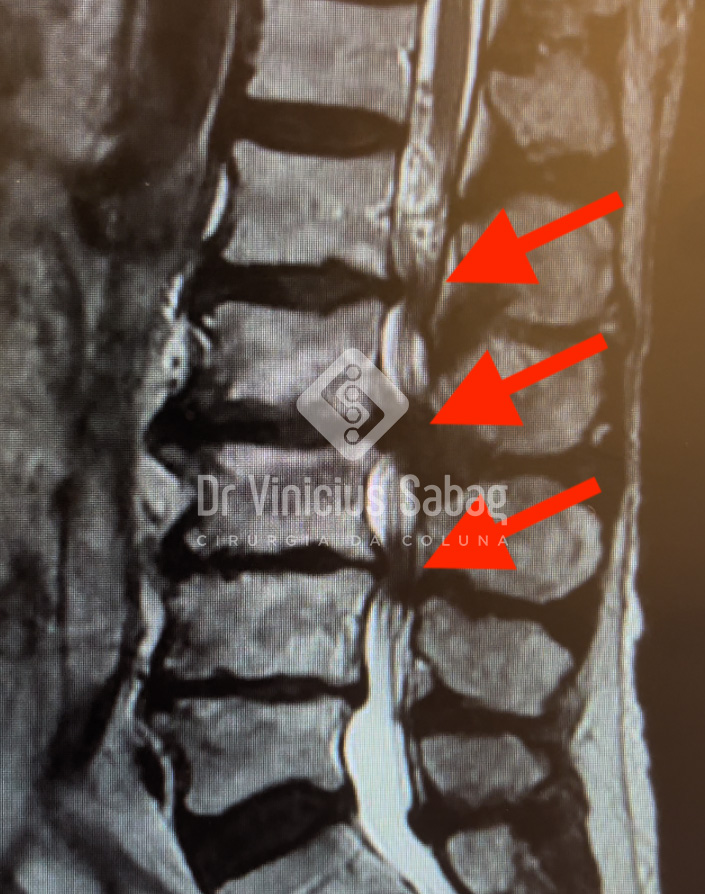

A ressonância magnética evidenciou o diagnóstico de estenose de canal lombar multinível, condição em que ocorre compressão dos nervos da coluna em mais de um ponto. Essa compressão leva aos sintomas clássicos de claudicação neurogênica, caracterizada por dor, formigamento ou fraqueza nas pernas ao caminhar ou ficar em pé por algum tempo, com melhora ao se sentar ou inclinar o tronco para frente — um sinal típico desse tipo de compressão nervosa.

Ressonância magnética evidenciando compressão dos nervos multinível.